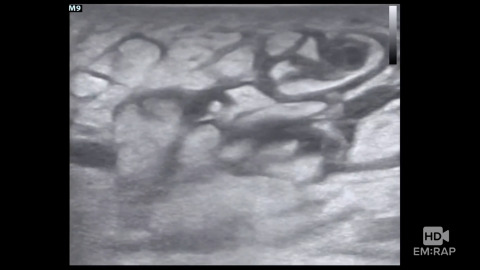

Subcutaneous Tissue Ultrasound

How to use ultrasound for the evaluation of abscess, cellulitis, and necrotizing soft tissue infections. Presented by Jacob Avila, MD.